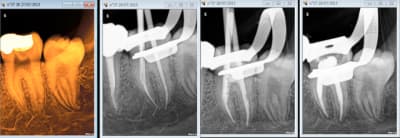

Ca c'est pas mal non plus en 45 mn, on se demande pourquoi thermo compacer au mac spadden et j'ai perdu un morceau de crochet au passage ! -)))))

Capture d e cran 2015 07 30 12.41 - Eugenol

Capture d e cran 2015 07 30 12.49 - Eugenol

Capture d e cran 2015 07 30 12.52 - Eugenol

Capture d e cran 2015 07 30 12.48 - Eugenol

Endo 16 + sc 33. Costeaude la racine DV.

Capture d e cran 2015 07 30 15.33 - Eugenol

une 37 .......

Capture d e cran 2015 07 30 16.22 - Eugenol

Ca m'arrive de foirer mais rarement, ici racine distale de 16 manque 2 mm. je n'essaie pas de forcer outre mesure et d'arriver à tout prix à l'apex.

Capture d e cran 2015 07 30 16.30 - Eugenol